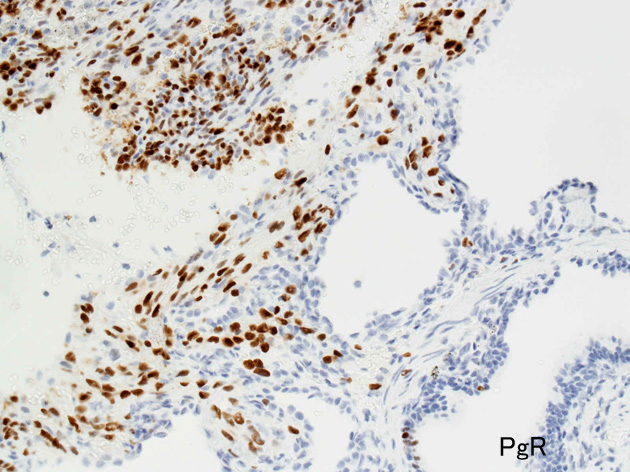

免疫染色

ER.jpg

PgR.jpg

Estrogen receptorProgesteron receptor